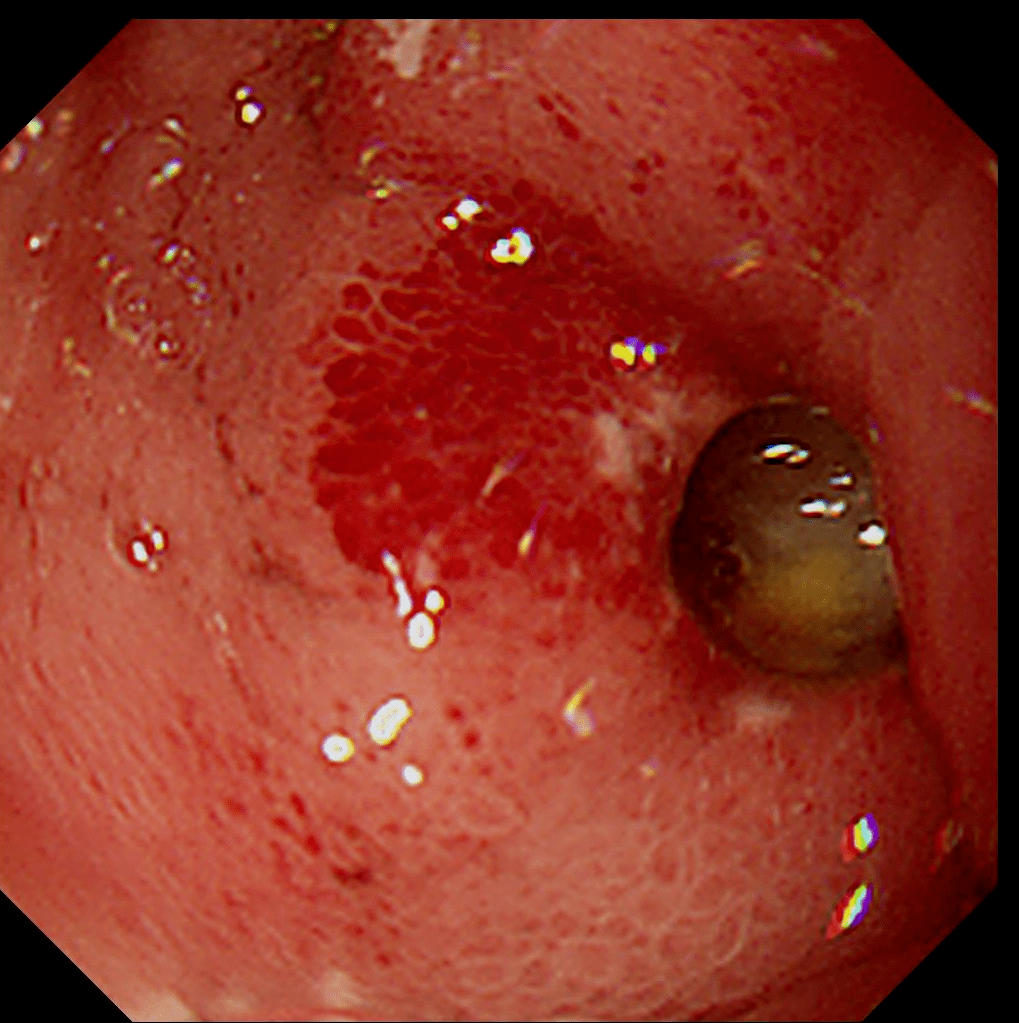

恶性胃溃疡

胃镜发现胃溃疡时需要取活检明确溃疡的良恶性,内镜下的表现也可以

可以直视观察溃疡,也可以进行活检,并根据病理检查结果作良恶性的鉴别

胃体发现不规则糜烂,溃疡时应取活检证实溃疡的良恶性.

请医生帮我分析下,这个应该是什么病,胃溃疡或者胃癌?